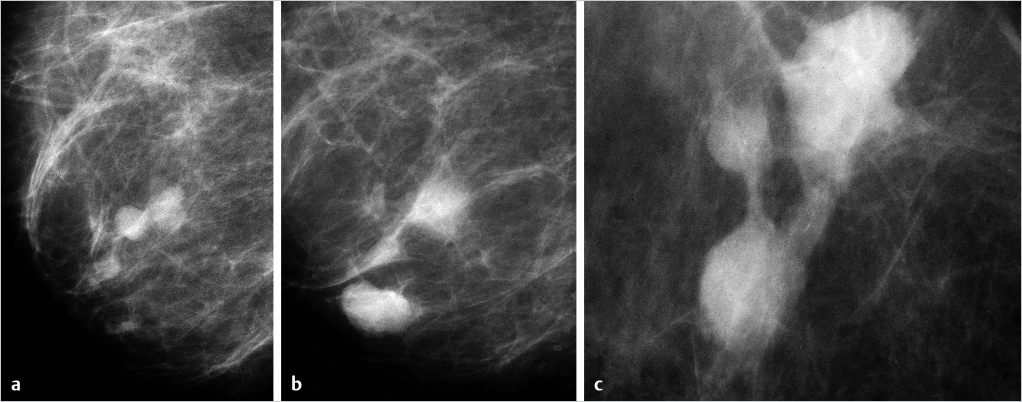

Example

This 82-year-old asymptomatic woman with a vaguely palpable lesion behind the right nipple presented for evaluation (▶Fig. 6.9).

Multifocal invasive stellate and/or circular lesions on the mammogram. ▶Fig. 6.9, ▶Fig. 6.10, and ▶Fig. 6.11 are examples of a multifocal invasive AAB.